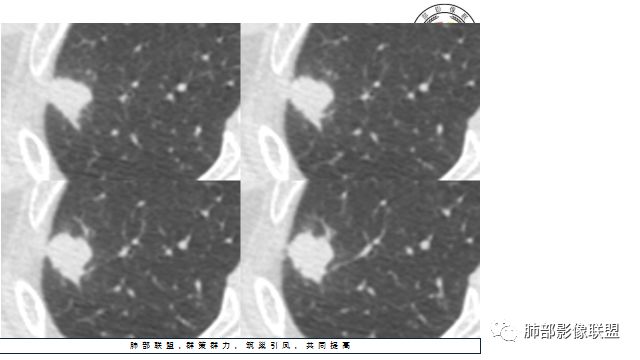

晨读:患者中老年男性,咳嗽 咳痰伴痰中带血2天,发现右上肺结节入院。

胸CT:右上肺结节,病灶位于胸膜下,边缘可见平直 u型征 软毛刺 晕,增强可见延迟强化,病灶中心低密度区。

2.右肺尖类圆形结节影,边界清楚,未见明显分叶或深切迹,部分分边缘较平直,可见细长毛刺棘状突起,相邻胸膜增厚,未见胸膜凹陷。后段胸膜下见条索影及微小结节影。

相关血管未见脐凹,有限图像层面未能显示相关支气管情况。